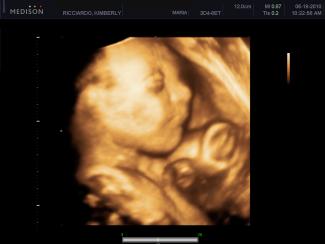

„Po dvoch minútach rozhovoru som vedela, že nemám to srdce ísť na potrat,“ napísala Nancy. „Možno som ani nikdy nemala. Pozrela som sa na ultrazvuk a bola som v šoku, že dieťa má nohy a hlavu. Pred štyrmi týždňami v ordinácii môjho lekára vyzeralo ako zrniečko ryže. Vyšla som na slnko a zistila som, že mám iné dieťa.“

Kým sa podobné príbehy v krízových centrách pre tehotné opakujú tisícráz za rok, nie všetky ženy majú to šťastie, že majú možnosť ísť na ultrazvuk, keď vkročia na potratovú kliniku. Najmenej 24 štátov má nejakú formu zákona regulujúcu použitie ultrazvuku počas interupčného zákroku, ale jednotlivé požiadavky sa medzi sebou veľmi líšia.

Nedávno štát Virginia uzákonil zákon požadujúci, aby ženy, ktoré chcú ísť na potrat, išli na ultrazvuk minimálne 24 hodín pred potratom a dostali možnosť vidieť aj ultrazvukový snímok. V Arkansase sú však lekári iba požiadaní, aby informovali ženu o jej práve pozrieť si ultrazvukový snímok, ak plánujú počas interrupčného výkonu použiť techniku.

Podľa Americans United for Life (AUL) (Američania zjednotení pre život), prolife organizácie, ktorá je na čele podpory ultrazvukovej legislatívy, je však Nancyno rozprávanie jedno z mnohých pôsobivých príbehov, ktoré odhaľujú aký silný dosah môže mať ultrazvuk na rozhodnutie ženy, dokonca aj, keď sa tak stane na potratovej klinike.

„Matky poznajú silu ultrazvuku,“ povedala pre LifeSiteNews.com hovorkyňa AUL Kristi Hamrick. „Keď vidia svoje nenarodené dieťa, môžu k nemu pocítiť veľkú lásku a spojenie s ním. To ovplyvňuje ich rozhodovanie.“